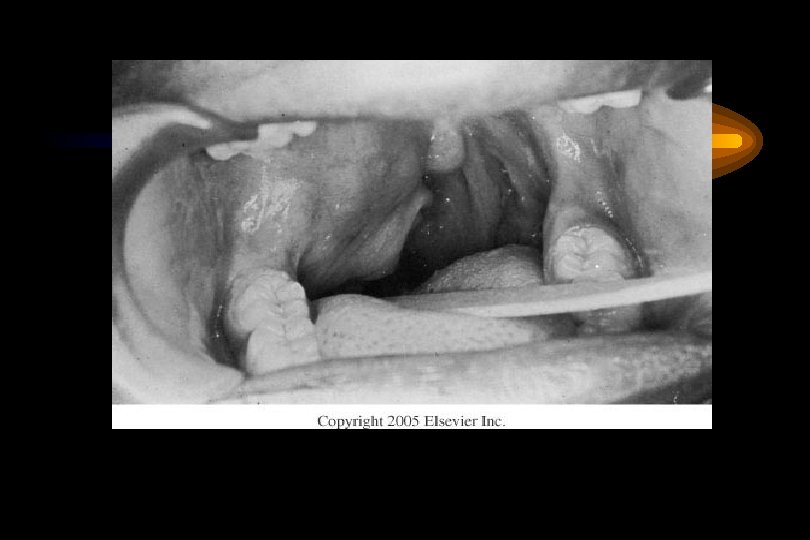

Mucoepidermoid Carcinoma • Presentation – Low-grade: slow growing, painless mass – High-grade: rapidly enlarging, +/- pain – **Minor salivary glands: may be mistaken for benign or inflammatory process • Hemangioma • Papilloma • Tori